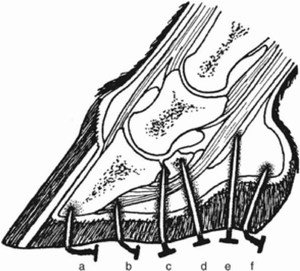

穿刺傷は、貫通した深さと足の部位によって分類されます。貫通の深さは、角質組織を貫通しただけの場合は表面的なもの、足底で1cm以上、蹄叉(ひづめの中心部の軟骨部)で1.5cm以上貫通した場合は深いものとなります。

深い傷は、その場所によって3つのタイプに分けられます。